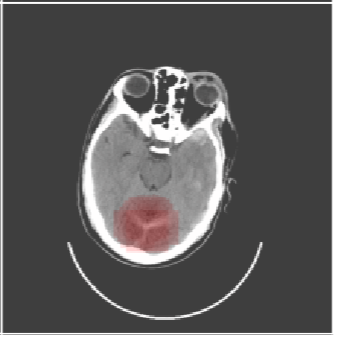

Inverse Problems in Neuroscience: Susceptibility Tensor Imaging

Inverse Problems in Radiology